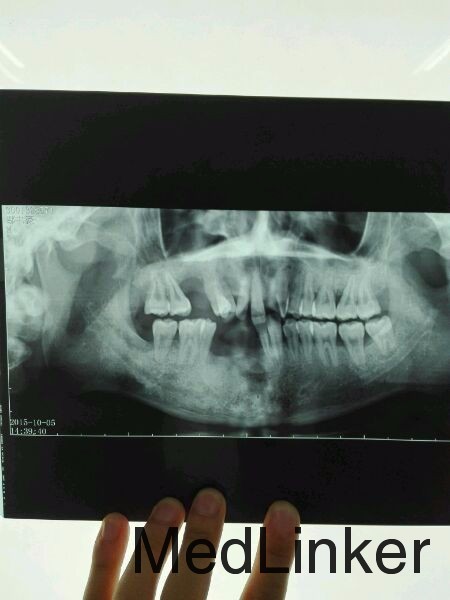

牙齿骨性脱落 种植

患者 男 25岁 牙齿脱落多颗,情况教严重;望专业医师上门协商解决方案。